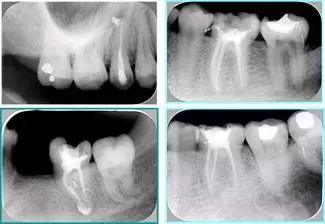

2. X 线片

共有 4 张 X 线片,分别是术前、诊断丝 、主牙胶尖确认、术后。

( 1 )术前:术前 X 线片用来了解牙齿的大概情况。术前预期为多根牙时 X 线片应偏头拍摄。

( 2 )诊断丝:根据术前 X 线片进行开髓、根管的初步预备后,需要插入诊断丝,用来指示工作器械位置。常用 10 号或 15 号扩大器作为诊断丝插入牙髓腔。

( 3 )主牙胶尖确认:通过术前预期和诊断丝诊断,明确工作长度、牙根走向,进行根管预备。之后应进行主牙胶尖(中锉)确认,已明确根管是否适合充填。

( 4 )术后:观察治疗效果。